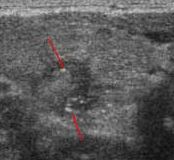

갑상샘 석회화란?석회는 조직과 세포로 칼슘이 비정상적으로 증식한 것으로, 초음파 검사로 흰색 점, 선과 응집된 형태 등으로 나타납니다.갑상샘 석회화는 초음파 검사로 분포의 정도, 모양, 크기, 위치 등을 통해서 양성인지 악성인지 진단합니다.양성 석회화는 표면이 분명하고 규칙적인데 악성 석회화는 거대 석회화의 경우나, 흰 점이 있었으며 크기가 매우 작은 소견이 보이지만 미세 석회화의 경우 깨끗이 제거하는 것이 어려운 재발 가능성이 높습니다.

▶ 좌) 불균일한 결절 내부에 미세석회화를 여러 개 볼 수 있는 악성결절, 우측) 2mm 이상의 거대석회화를 볼 수 있는 악성결절(출처: 서울대암병원)